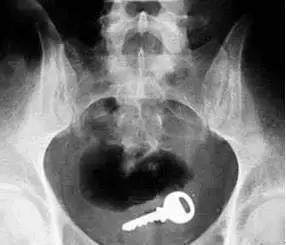

听完家长的描述和初步检查后,医生怀疑这是异物没有及时发现引起的。随后,经X光片检查,发现孩子阴道部位有一个带齿状的不规则长方体金属异物。菲菲随后接受了手术治疗。

医生在菲菲阴道内取出了一个2厘米左右长的金属钥匙!医生将取出的异物给菲菲父母看时,他们顿时一脸懵逼,惊诧不已!好在孩子术后情况明显好转,再也闻不到恶臭的气味,肚子也不再隐隐作痛了。事实上,类似菲菲 这样的案例已经不是第一次发生,假如菲菲没有找到病因,让蜡笔留在体内,很可能会导致子宫或宫颈部位病变,进而影响生育能力,造成一辈子的遗憾。